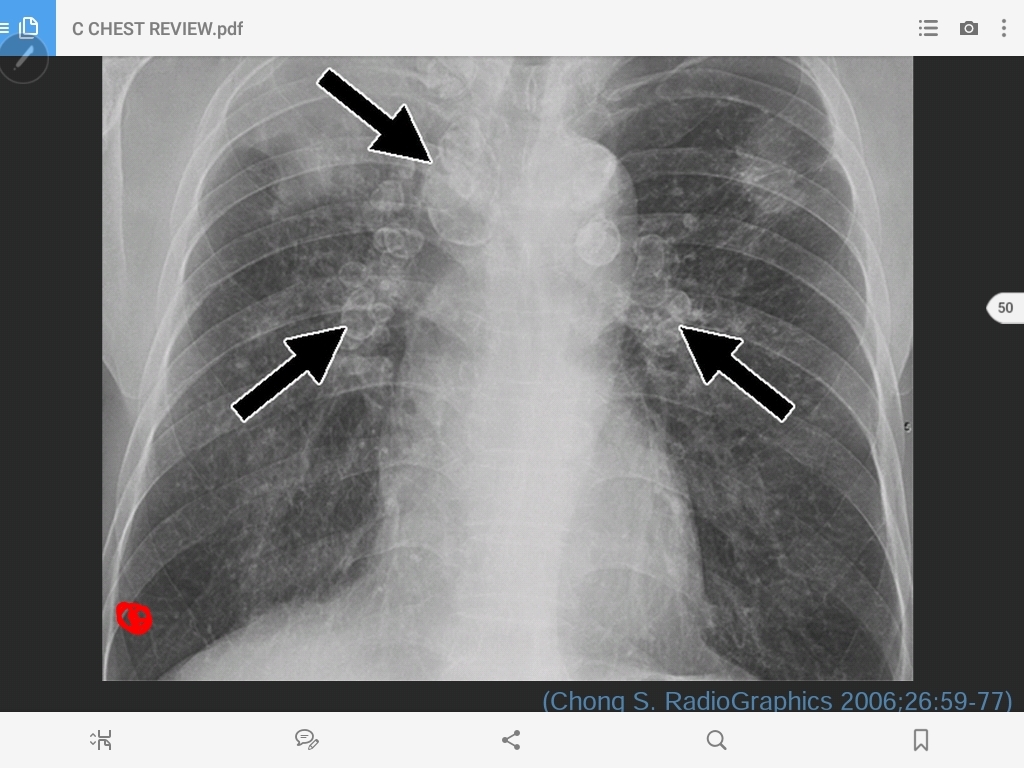

pulmonary metastasis